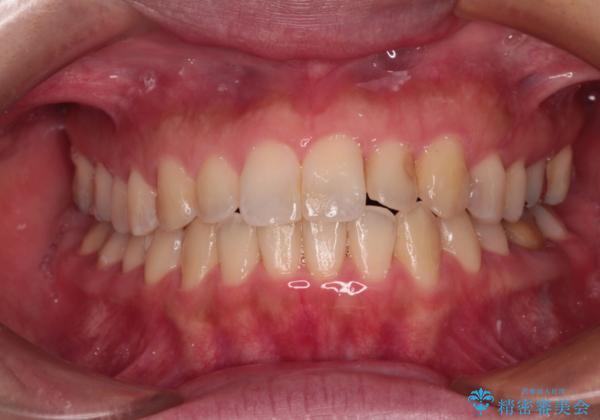

- 前歯の捻れを気にして来院された患者様です。

上顎前歯が捻れて前方に飛び出しており、下顎前歯もそれに沿うようにデコボコとなっていました。

IPR(歯と歯の間を削る処置)によりスペースを獲得して上下前歯のデコボコを改善し、インビザラインにて矯正治療を行うこととしました。

捻れていた前歯の形態が、先端が欠けていたり、一部むし歯処置により左右非対称の形態となっていたため、なかなかゴールが定まらず、治療期間がかかってしまいました。